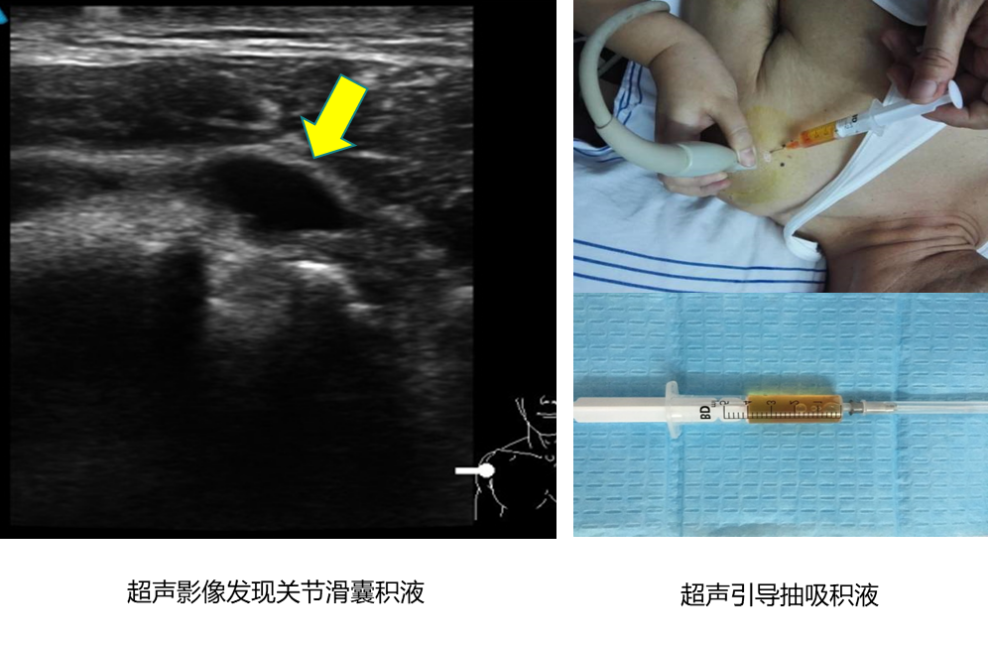

? ? ? ?關(guān)節(jié)囊及其周?chē)綄夙g帶、肌腱、滑囊等部位的急、慢性損傷病變;

? ? ? ?可視下引導(dǎo)注射或抽吸治療,精準(zhǔn)到達(dá)目標(biāo)部位,可避免損傷周?chē)?、神?jīng)、肌腱等。對(duì)于檢查發(fā)現(xiàn)的問(wèn)題,可進(jìn)行關(guān)節(jié)腔積液抽吸、精準(zhǔn)注射玻璃酸鈉、類(lèi)固醇激素、增生液、富血小板血漿(PRP)等。